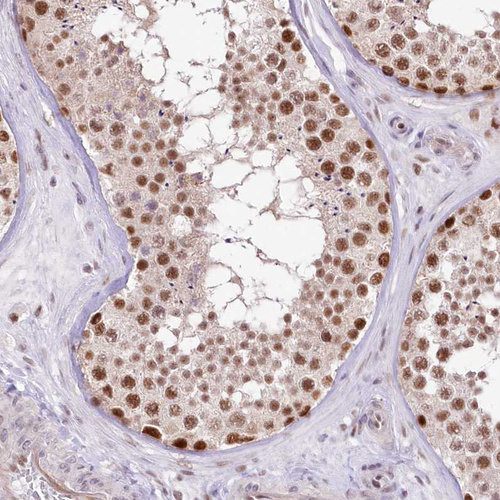

Immunohistochemical staining of human testis shows moderate to strong nuclear positivity in cells in seminiferous ducts.